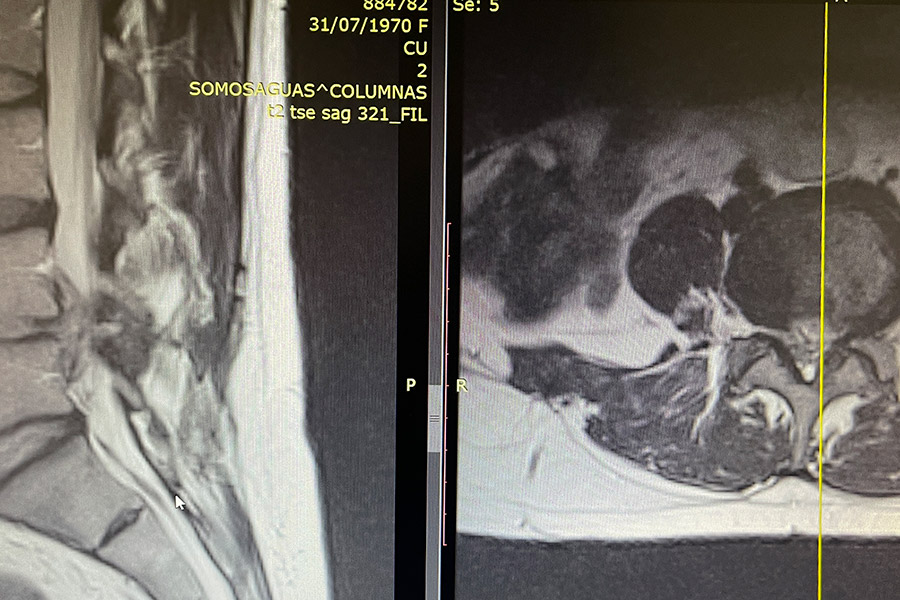

Caso clínico: endoscopia de columna multinivel L4L5 y L5S1

Los síntomas que presentaba el paciente eran dolores acentuados en las piernas, claudicación a la marcha y calambres y hormigueos en las piernas.

Durante la intervención quirúrgica, se abordarán los dos niveles mediante la técnica de endoscopia de columna.